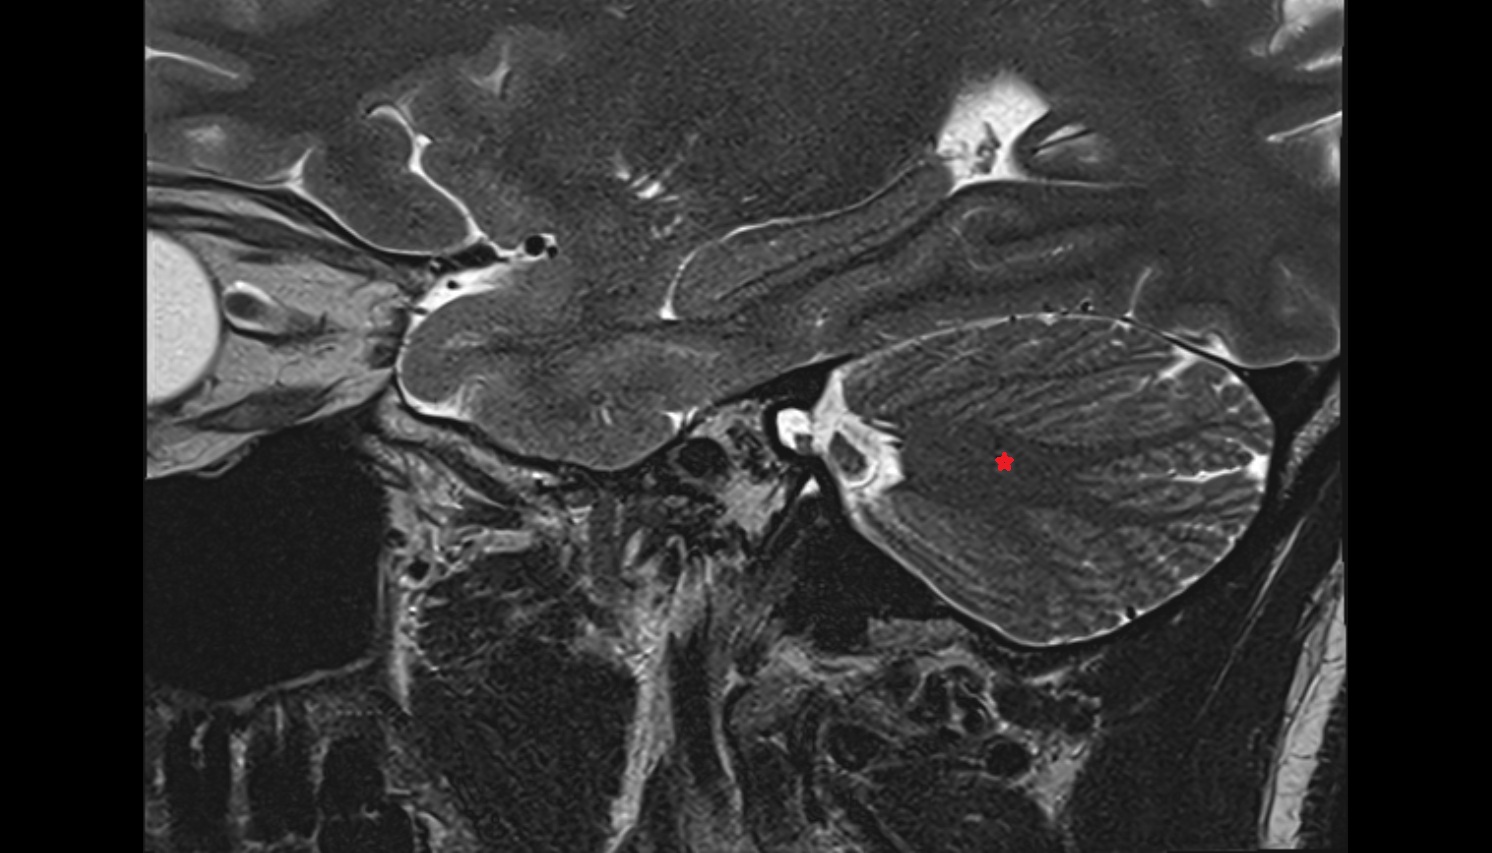

- Cerebellar tonsil (H IX)

- Crus I of ansiform lobule of cerebellum

- Crus II of ansiform lobule of cerebellum

- Paramedian lobule (HVII) of cerebellum

- Biventral lobule (HVIII) of cerebellum

- Intrabiventral Fissure of Biventral Lobule

- Lunogranicile fissure of cerebellum